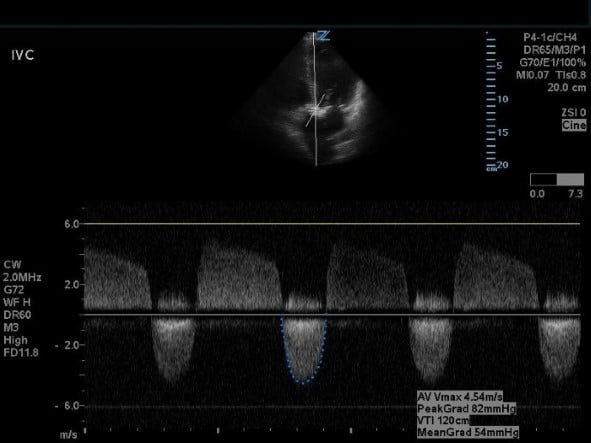

Figure 5. Apical five-chamber view with continuous wave doppler on the AV.

- Obtain AV measurements with continuous wave doppler (CWD) through the AV. Trace the downward, systolic waveform to calculate the AV VTI and peak aortic velocity (Vmax).

An AV area <1.0 cm2, peak aortic velocity >4 m/s, mean transaortic gradient >40 mmHg is diagnostic for critical AS, however, in cases of depressed ejection fraction, AV area <1.0 cm2 can be the only abnormal parameter.7